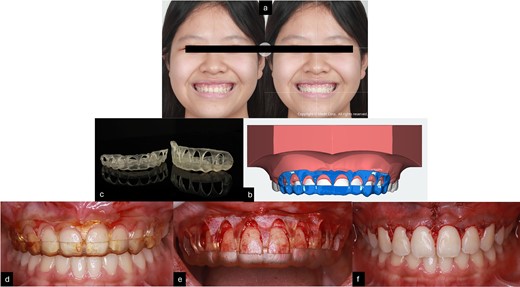

(a) Smile design before gingivoplasty treatment; (b) 3D printing gingivoplasty guide; (c) 3D guide design; (d,e) gingivoplasty treatment with guide; (f) post-treatment.

The crown-root ratio of the upper front teeth can be adjusted by removing enough bone while maintaining the biologic width. This involves two procedures: osteotomy, which entails removing enough bone while maintaining the biologic width, and osteoplasty, which involves curving the alveolar crests, creating lateral grooves, and thinning the bone border. To make the surgery simpler and more controlled, 2D smile design [8] on smile picture a 3D simulation, and an 3D guide design [9] were used to create a surgical guide for the gingivoplasty procedure. The treatment was performed by periodontist with laser for gingivectomy and handpiece for gingivoplasty (Fig. 4).